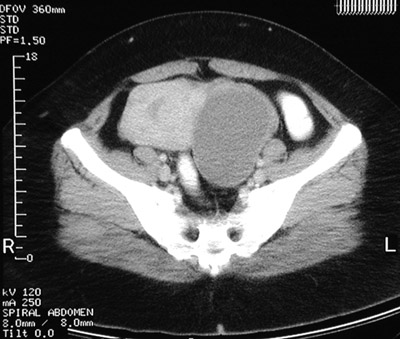

| These CT scan views of the pelvis demonstrate a uterus containing leiomyomata. The view above reveals a submucosal leiomyoma while the view below shows an intramural leiomyoma of the upper fundus. The fluid-filled structure on the left that is displacing the uterus to the left is an endometrioma of the ovary. |